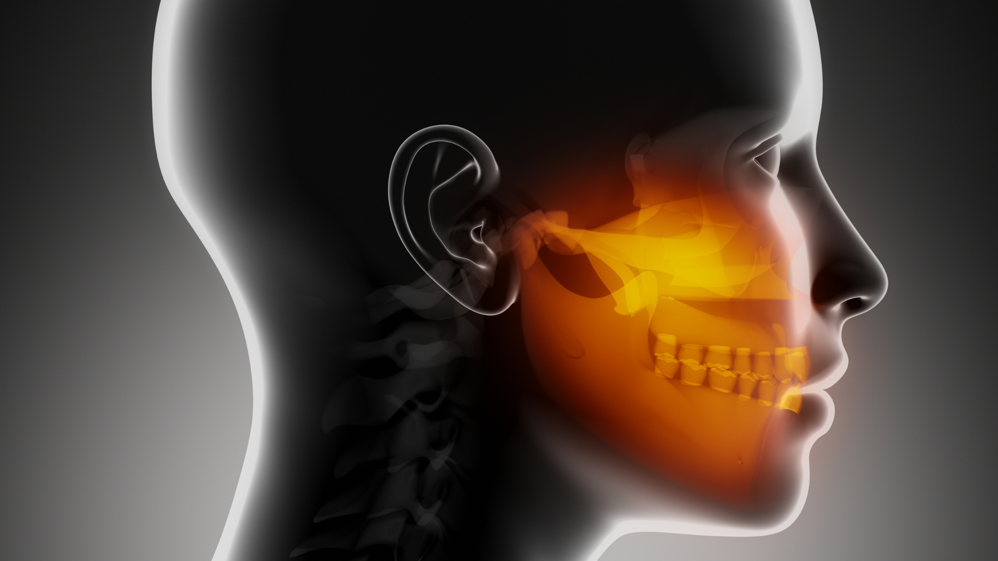

Affrontiamo con competenza disturbi come malocclusione, dolori mandibola, disturbi temporomandibolari e disfunzioni cranio-mandibolari, offrendo bite gnatologici su misura e soluzioni efficaci per dolore mandibola orecchio cranio, difficoltà apertura bocca e disturbi articolazione mandibola.

Il collegamento tra mandibola e postura è al centro della nostra attività: trattiamo vertigini problemi mandibola, mal di schiena mandibola, postura mandibola cervicale, abitudini viziate postura e mal appoggio piede mandibola con approccio integrato.